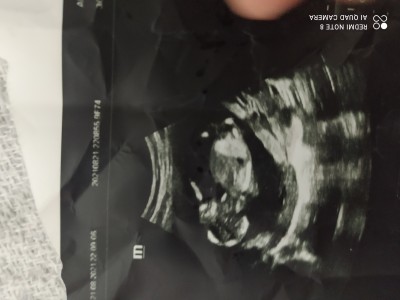

Arkadaşlar 14+2 haftalık ultrason resmim tahmini olan var mı

Gebelik haftası 14+2

Erkek gibi ama doktor bisey demedi mi özelde söylüyorlar hemen

Özele gittim 13. Haftada erkek dedi sonra kız dedi sonra tekrar erkek dedi ama 16. Haftada kesin söyleyim dedi o yuzden emin olamadik nerden anladkniz erkek olduğunu acaba

Benim doktorum erkek bebeklerin kafası biraz büyük oluyor dedi:) kizlar biraz daha cılız oluyormuş yapı olarak